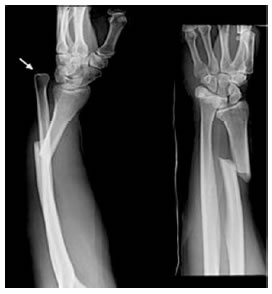

X-Quang:

Phim X-quang xác định có gãy xương trụ 1/3 trên và trật chỏm xương quay (mất khe khớp cánh tay – quay)

-Gãy Galeazzi = Gãy 1/3D thân xương quay có di lệch gập góc/di lệch chồng + Sai khớp quay trụ dưới.

2. Cận lâm sàng: Xq cẳng tay-cổ tay thẳng - nghiêng: chẩn đoán xác định.